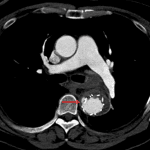

- Surgical changes of endograft repair of the distal aortic arch and descending thoracic aorta with aneurysmal dilation of the aorta measuring up to 4.5 x 4 cm transaxially in the proximal descending aorta

- Focal area of contrast leakage through the interstices of the graft along the medial aspect of the distal graft in the proximal descending aorta with diffuse soft tissue thickening about the graft

- Type III aortic endoleak

Small type III aortic endoleak in the proximal descending thoracic aorta. Aneurysmal dilation of the arch and descending aorta measuring up to 4.5 cm in diameter.

Soft tissue thickening along the length of the graft is nonspecific and while this could relate to the endoleak, aortitis/endograft infection could have a similar appearance.